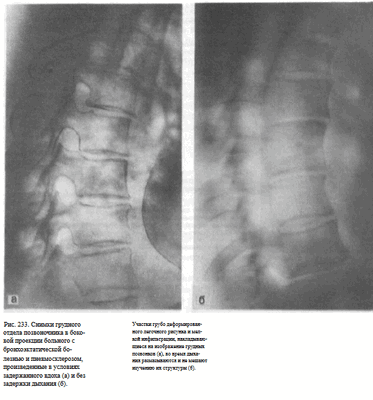

При правильно выбранных технических условиях съемки и отсутствии динамической нерезкости в случаях выполнения рентгеновского снимка без задержки дыхания контуры позвонков получаются резкие, четко видна костная структура позвонков без наслоения на них (возможного) изображения легочного рисунка.